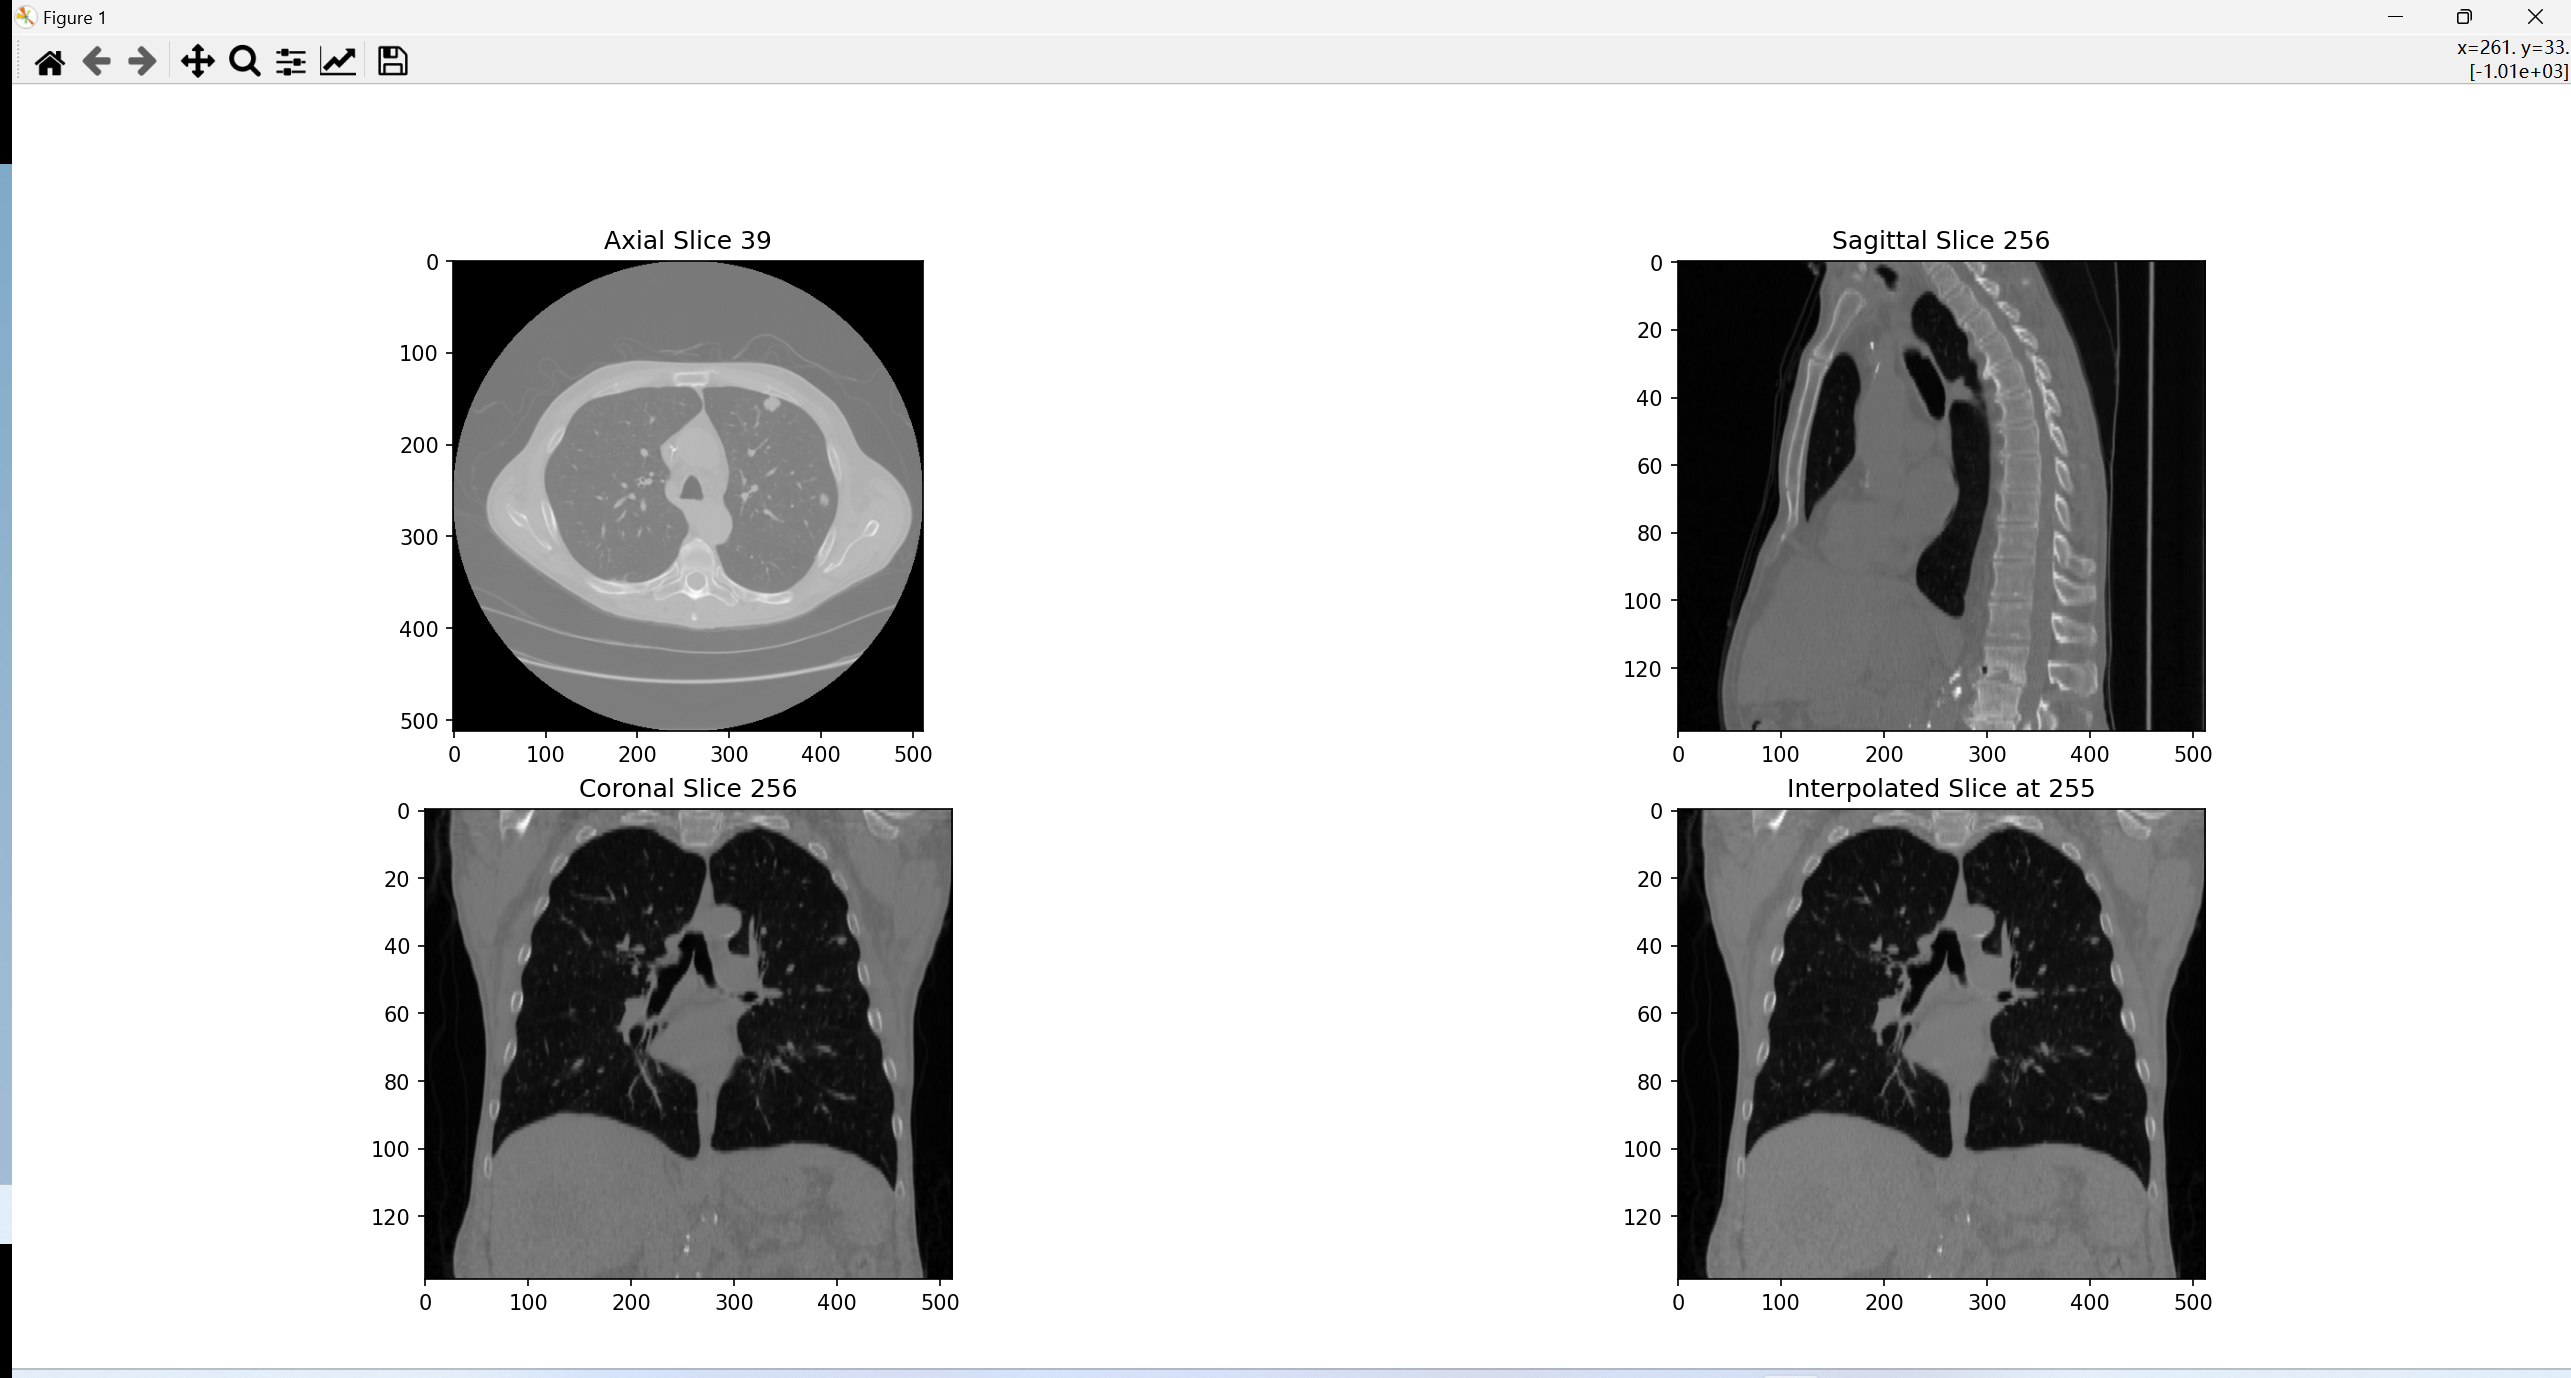

效果图显示